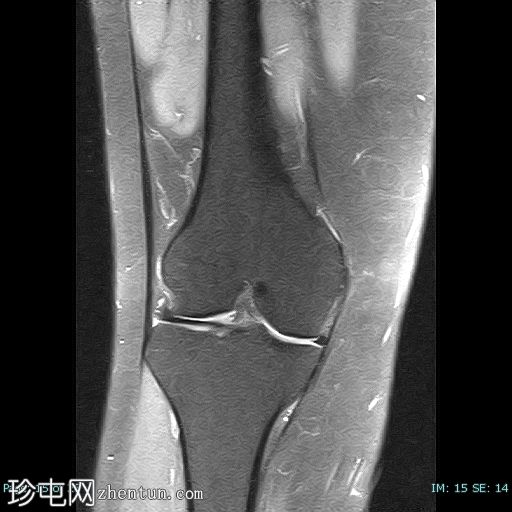

冠状位

T2加权像

髌骨高位(Insall-Salvati比值=1.7),伴外侧半脱位。内侧髌骨支持带及内侧髌股韧带变薄、缺损、松弛。

外侧髌骨关节面软骨内T2/STIR/PD信号强度增高,伴下方骨髓囊性改变和水肿。

外侧Hoffa脂肪垫水肿。

外侧髌骨关节面软骨软化。

本病例展示了霍夫脂肪垫撞击综合征的典型特征,伴有髌骨高位和髌骨外侧半脱位。

患者症状最常见的潜在病因被认为是髌骨轨迹异常。